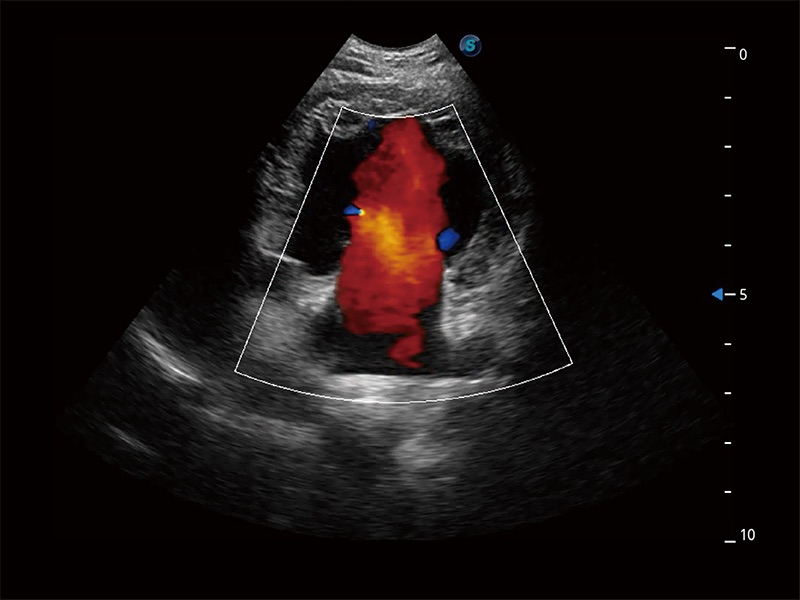

在传统二维血流成像的基础上,呈现血流的立体感,具有动感的生命力之美。即便是微小的血管也能轻松应对,提高了血流的视觉敏感性。

极大提升超低速微细血流的检出能力,同时更精准地滤除软组织和超声信号,为兽用医生提供以往无法通过常规血流获得的疾病诊断信息。